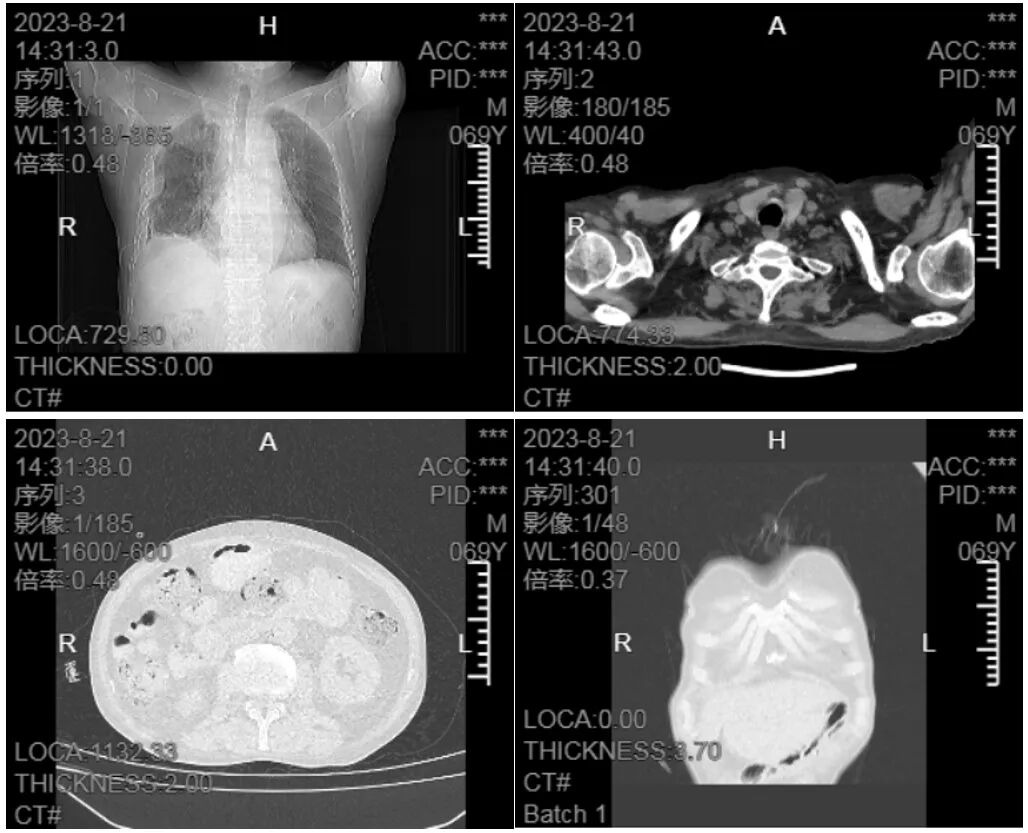

8月21日胸腔穿刺置管术后行CT胸部平扫+三维重建(冠状位)检查提示:1.右肺多发病变,较2023-08-12片无明显变化;右侧胸膜增厚;右侧胸腔积液,局部包裹,较前略吸收;右侧气胸较前新增。2.冠状动脉钙化。见图6。

▲图6 胸腔穿刺置管术后CT胸部平扫+三维重建(冠状位)